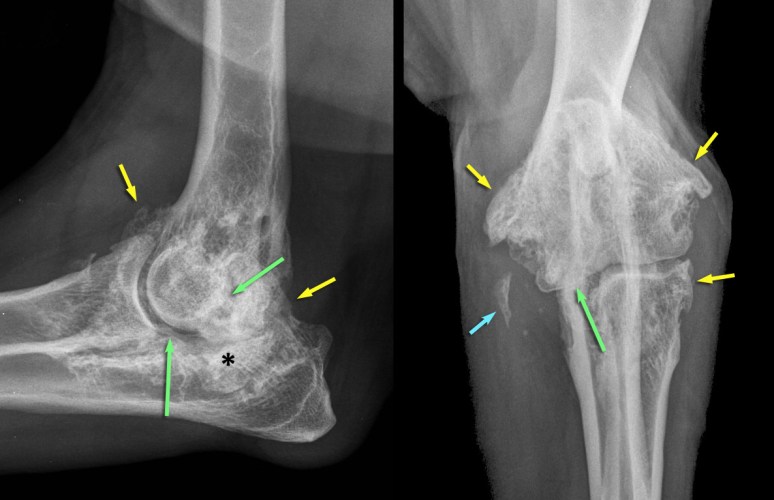

RadioQuiz 8 – Réponse

On note d’abord une prolifération osseuse périarticulaire marquée (flèches jaunes), dont le contour est irrégulier mais bien défini, indiquant un processus inactif à faiblement actif. Cette prolifération est compatible avec une ostéophytose (i.e. aux marges articulaires, à la jonction synoviale/capsulaire) et/ou enthésophytose (i.e. à l’intérieur des tissus mous périarticulaires, au site d’insertion dans l’os = enthèse). Quelques foyers minéraux amorphes sont situés médialement au coude (flèche bleue), impliquant probablement le ou les tendons fléchisseurs du coude s’insérant sur l’épicondyle huméral médial situé plus haut. Les marges sous-chondrales (flèches vertes) sont irrégulières et l’espace articulaire est hétérogène par endroit (notamment sous le processus anconé). Une incongruence articulaire est suspectée, alors que le processus coronoïde latéral est plus haut que la tête radiale sur la vue latérale (flèche verte) et que le processus coronoïde médial est mal défini et semble plus haut que la tête radiale sur la vue cranio-caudale (flèche verte). Finalement, on note une sclérose (*) sous-chondrale à l’incisure ulnaire. Ces changements sont compatibles avec de l’ostéoarthrose sévère, vraisemblablement secondaire à une dysplasie du coude (incongruence et fragmentation du processus coronoïde médial). Les marges articulaires ne montraient pas de lyse sous-chondrales, ce qui aurait permis de suspecter une arthrite rhumatoïde. Il n’a pas de lyse au site d’insertion de la capsule articulaire pour suggérer une tumeur agressive des tissus mous articulaires, ni de lyse médullaire ou corticale pour suggérer un ostéosarcome. Une arthrite septique aurait aussi engendré des changements mal définis (alors que la prolifération dans ce cas est bien définie) et une lyse sous-chondrale devrait être visible assez tôt dans le processus.

On note d’abord une prolifération osseuse périarticulaire marquée (flèches jaunes), dont le contour est irrégulier mais bien défini, indiquant un processus inactif à faiblement actif. Cette prolifération est compatible avec une ostéophytose (i.e. aux marges articulaires, à la jonction synoviale/capsulaire) et/ou enthésophytose (i.e. à l’intérieur des tissus mous périarticulaires, au site d’insertion dans l’os = enthèse). Quelques foyers minéraux amorphes sont situés médialement au coude (flèche bleue), impliquant probablement le ou les tendons fléchisseurs du coude s’insérant sur l’épicondyle huméral médial situé plus haut. Les marges sous-chondrales (flèches vertes) sont irrégulières et l’espace articulaire est hétérogène par endroit (notamment sous le processus anconé). Une incongruence articulaire est suspectée, alors que le processus coronoïde latéral est plus haut que la tête radiale sur la vue latérale (flèche verte) et que le processus coronoïde médial est mal défini et semble plus haut que la tête radiale sur la vue cranio-caudale (flèche verte). Finalement, on note une sclérose (*) sous-chondrale à l’incisure ulnaire. Ces changements sont compatibles avec de l’ostéoarthrose sévère, vraisemblablement secondaire à une dysplasie du coude (incongruence et fragmentation du processus coronoïde médial). Les marges articulaires ne montraient pas de lyse sous-chondrales, ce qui aurait permis de suspecter une arthrite rhumatoïde. Il n’a pas de lyse au site d’insertion de la capsule articulaire pour suggérer une tumeur agressive des tissus mous articulaires, ni de lyse médullaire ou corticale pour suggérer un ostéosarcome. Une arthrite septique aurait aussi engendré des changements mal définis (alors que la prolifération dans ce cas est bien définie) et une lyse sous-chondrale devrait être visible assez tôt dans le processus.

RadioQuiz 8

Signalement: Berger allemand, femelle stérilisée, 10 ans.

Histoire clinique: Boiterie et douleur à la palpation du coude gauche.